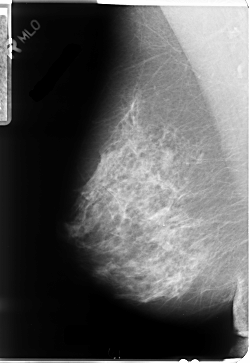

B_3054_1.LEFT_MLO

LEFT_MLO LINES 4760 PIXELS_PER_LINE 3240 BITS_PER_PIXEL 12 RESOLUTION 50 NON_OVERLAY